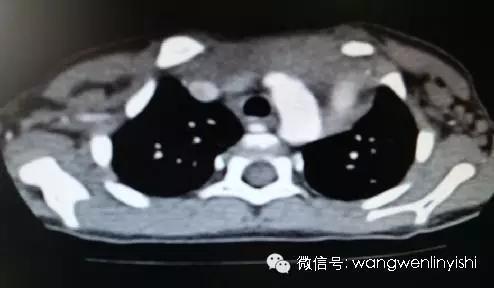

患儿3岁,自幼发现胸骨上半裂开,经检查发现先天性心脏病,室间隔缺损。术前查体发现胸骨上半完全裂开,中间明显凹陷,可以看到心脏搏动。心前区可闻及收缩期杂音。CT检查发现胸骨上半正常结构消失,两侧肋软骨与裂开的胸骨相连。心脏超声提示室间隔缺损。

(胸骨上半裂开)

(裂开的中部深面为主动脉弓)

(下半胸骨连接部分仅2公分)